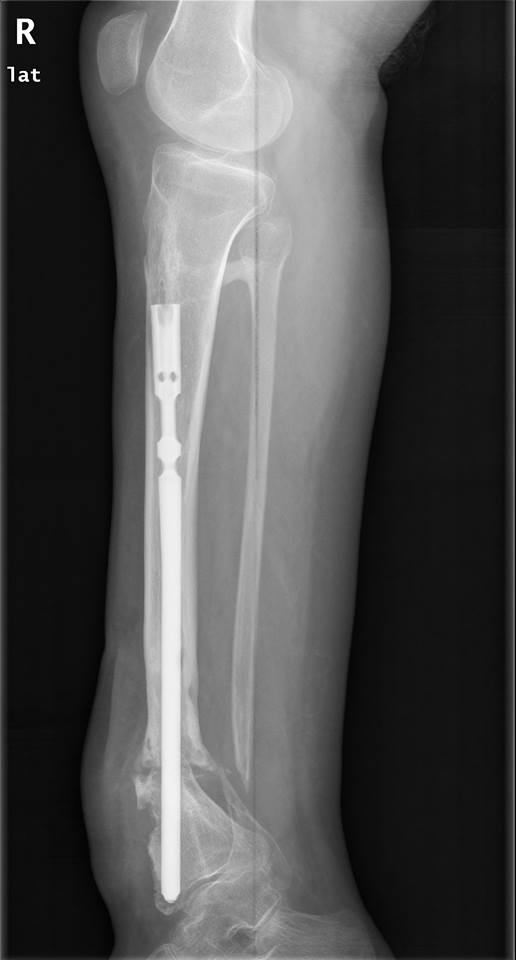

Уважаемые коллеги,Есть девушка с таким вот гвоздиком.

В плане - удаление и реостеосинтез.Вопрос - как минимально инвазивно удалить это чудо? Понимаю, что ранее вопрос поднимался, но тут мне кажется случай не стандартный.Спасибо.

Это UTN (Synthes) или его клон. То есть резьба M6.

Извлекли даже без ожидаемых приключений. Стержень от Илизаровского аппарата in vivo не полез (in vitro позже - как родной), но удалалка от нашего Медбиотеховского стержня зацепилась и все ушло вполне гладко. Спасибо за совет!

Закрыто деформация устранялась, но не полностью (и слегка поперечный компонтент смещения появлялся), поэтому и с учетом анамнеза открыли несращение с декортикацией, устранили деформацию, рассверлили, зафиксировали стержнем потолще и винтов дистально 4 штуки. Костная пластика (вскрывали канал фрезой, получили хороший столбик), шов. Снимки на неделе сделаем.